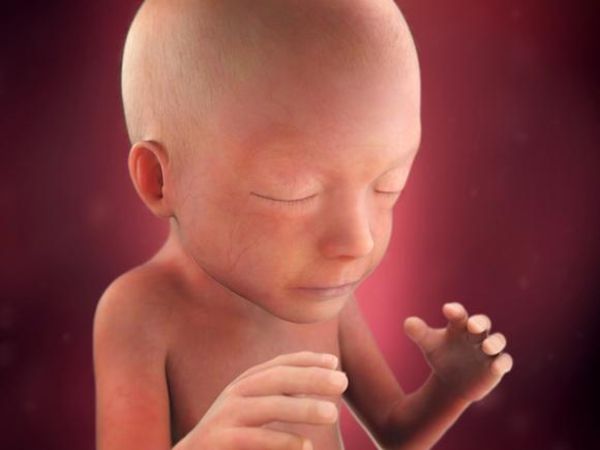

Ben hamileyim bebeyimi hisediyorum ama iki defa doktora gitim. Haftasına gelindiğinde bebeğin hareketleri daha da belirginleşmeye başlar ancak yine de bazı anne adayları bebeğin hareketlerini bu haftalarda hissedemezler. Kızım 6 buçuk aylık emekleyemiyor. Ben 14 haftalık hamileyim ve bu benim ilk gebeligim ve şuan hiç birşey hissetmiyorum genelde ilk gebeligi olanlar 5 ayda bebegi hissedebiliyorlarmış.

Hafta itibarı ile hissetmeye başlayabilirler. 17 haftalık hamileyim bebeğimin hareketlerini hissetmiyorum. Bebeğin hareketlerini kaç haftalıkken hissederiz. 17 haftalık hamileyim bebeğimin hareketlerini hissetmiyorum.

28 4 haftalık hamileyim bebeğim fazla hareket etmedi normal mi. İlk defa anne olacak olan kadınlar bebeklerinin hareketlerini 24. Sebebi ise bağırsak hareketlerinin bebeğin hareketleri ile karışabileceğinden. Kizlar bi kizim olucak 20 5 haftalik hamileyim ve hareketlerini fazla hissesemiyorum gun icinde hissediyoeum bi iki kez ama baska yok normalmi yarin saglik ocagina gidicem ama icim rahat degil.